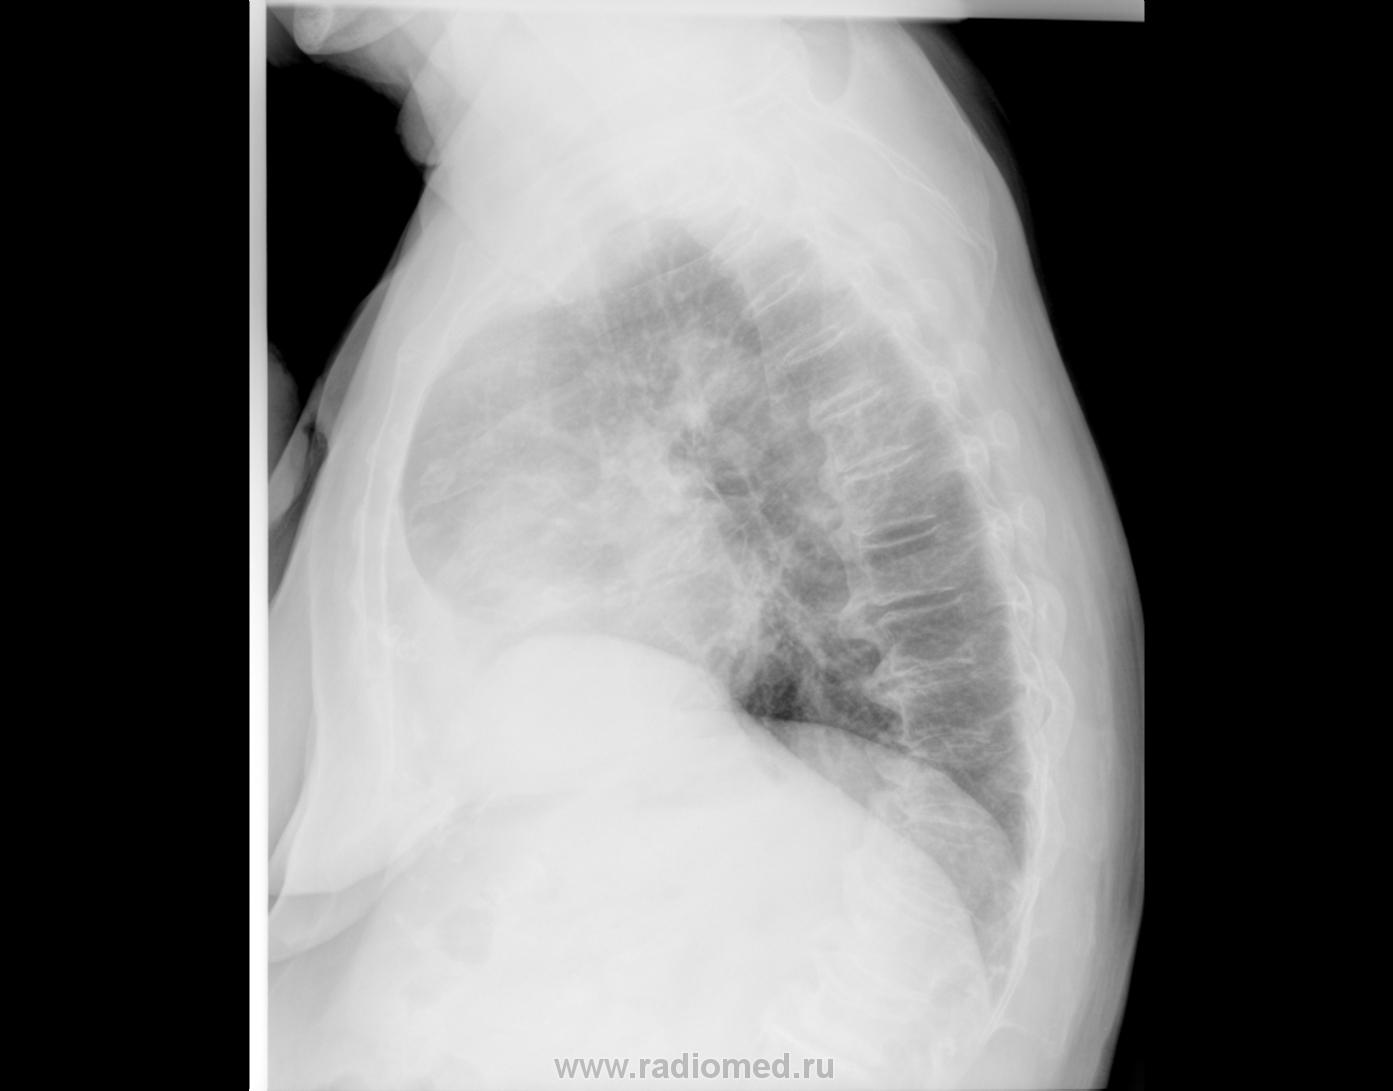

Вот еще правый боковой! Это "алаверды" Владимиру Борисовичу!

Итак. В прямой проекции .та "хрень" расположена центрально, этак почти "на тени " позвоночника.

Следовательно на боковой проекции "эта штука" должна быть видна очень хорошо или "спереди" или "сзади". А где она на боковом снимке?

А куда это "попер" купол диафрагмы?

Но "штуковина" значительных размеров, та, что "снаружи" лучше всего видна на косой (с небольшим поворотом прямой) проекции, следовавтельно, на мой взгляд, с топографией "неувязочка".

Диафрагма высоковато - пожилой человек... Косой снимок сделан не в стандартной проекции, это доктор под контролем рентгеноскопии "выводил" узел.